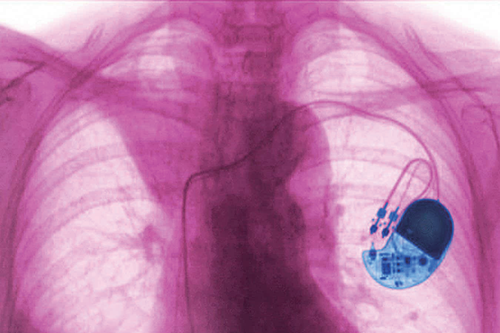

但好景不长。毕竟,目前用于修复身体损伤或应对功能衰退的植入设备都存在一个问题:不能永久耐用。无论是全球数量约为300万个的心脏起搏器,还是其他各类植入设备,都是如此。人工硬件与柔性的人体组织难以兼容,免疫系统会攻击这些外来物。

现代植入设备正是嵌入了这些电回路中。心脏起搏器维持心跳节律,脑深部电刺激装置释放电脉冲以改善帕金森病的症状,人工耳蜗通过刺激内耳神经使人恢复听力。目前,科研人员还在研发可助人恢复视力的视网膜植入设备。

不过,人体对不同植入设备的耐受度差异极大:心脏起搏器通常耐受性较好,电池可使用15年之久,但脑深部电刺激装置一般只能用3至5年。而伯克哈特的实验性大脑植入设备,曾创造了7年使用寿命的记录。